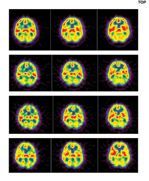

In 2005, a two part clinical study was carried out at University of Pennsylvania using SPECT (Single Photon Emission Computed Tomography) analysis to compare the effects of the 'M' Technique® to conventional (Swedish) massage. A radiopharmaceutical was injected intravenously into subjects before and after the intervention and 65 areas of the brain were compared. Significant differences emerged. The 'M' Technique® appeared to have a more profound effect and that effect increased when the 'M'® was repeated over time. The research was funded by the American Massage Foundation and the findings were presented at the American Massage Therapy conference in Cincinnati, OH in September 2007. The study was published in the Journal of Alternative and Complementary Medicine in October 2008. For abstract please click here. —Dr Jane Buckle PhD, MA, RN, Cert Ed